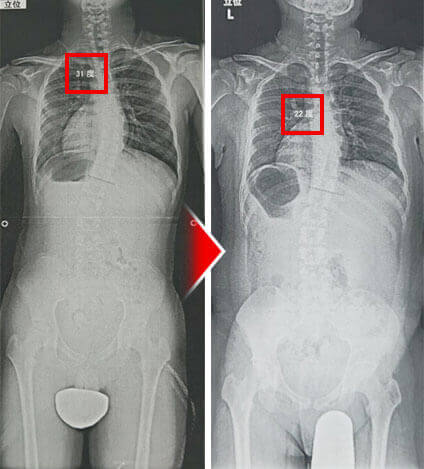

整形外科では一生治らないといわれている側弯症でも、たった1回、10分以内の施術でここまで変化してしまいます。しかも、背骨には刺激を加えない、触れる・撫でるだけの施術で出せた結果です。

医師も驚愕した治療効果。レントゲンでも明らかな変化が見られ、コブ角が31度から22度になり側弯症が治りました。

この治療法を2回受けた後の側弯症の変化です。背骨の変形を直に確かめても、C型の側弯がまっすぐに変化しています。

大学病院で再検査してもらったところ、背骨の歪みが31度から22度になっていました!側弯症は治癒で通院の必要もなくなり、本当によかったです!